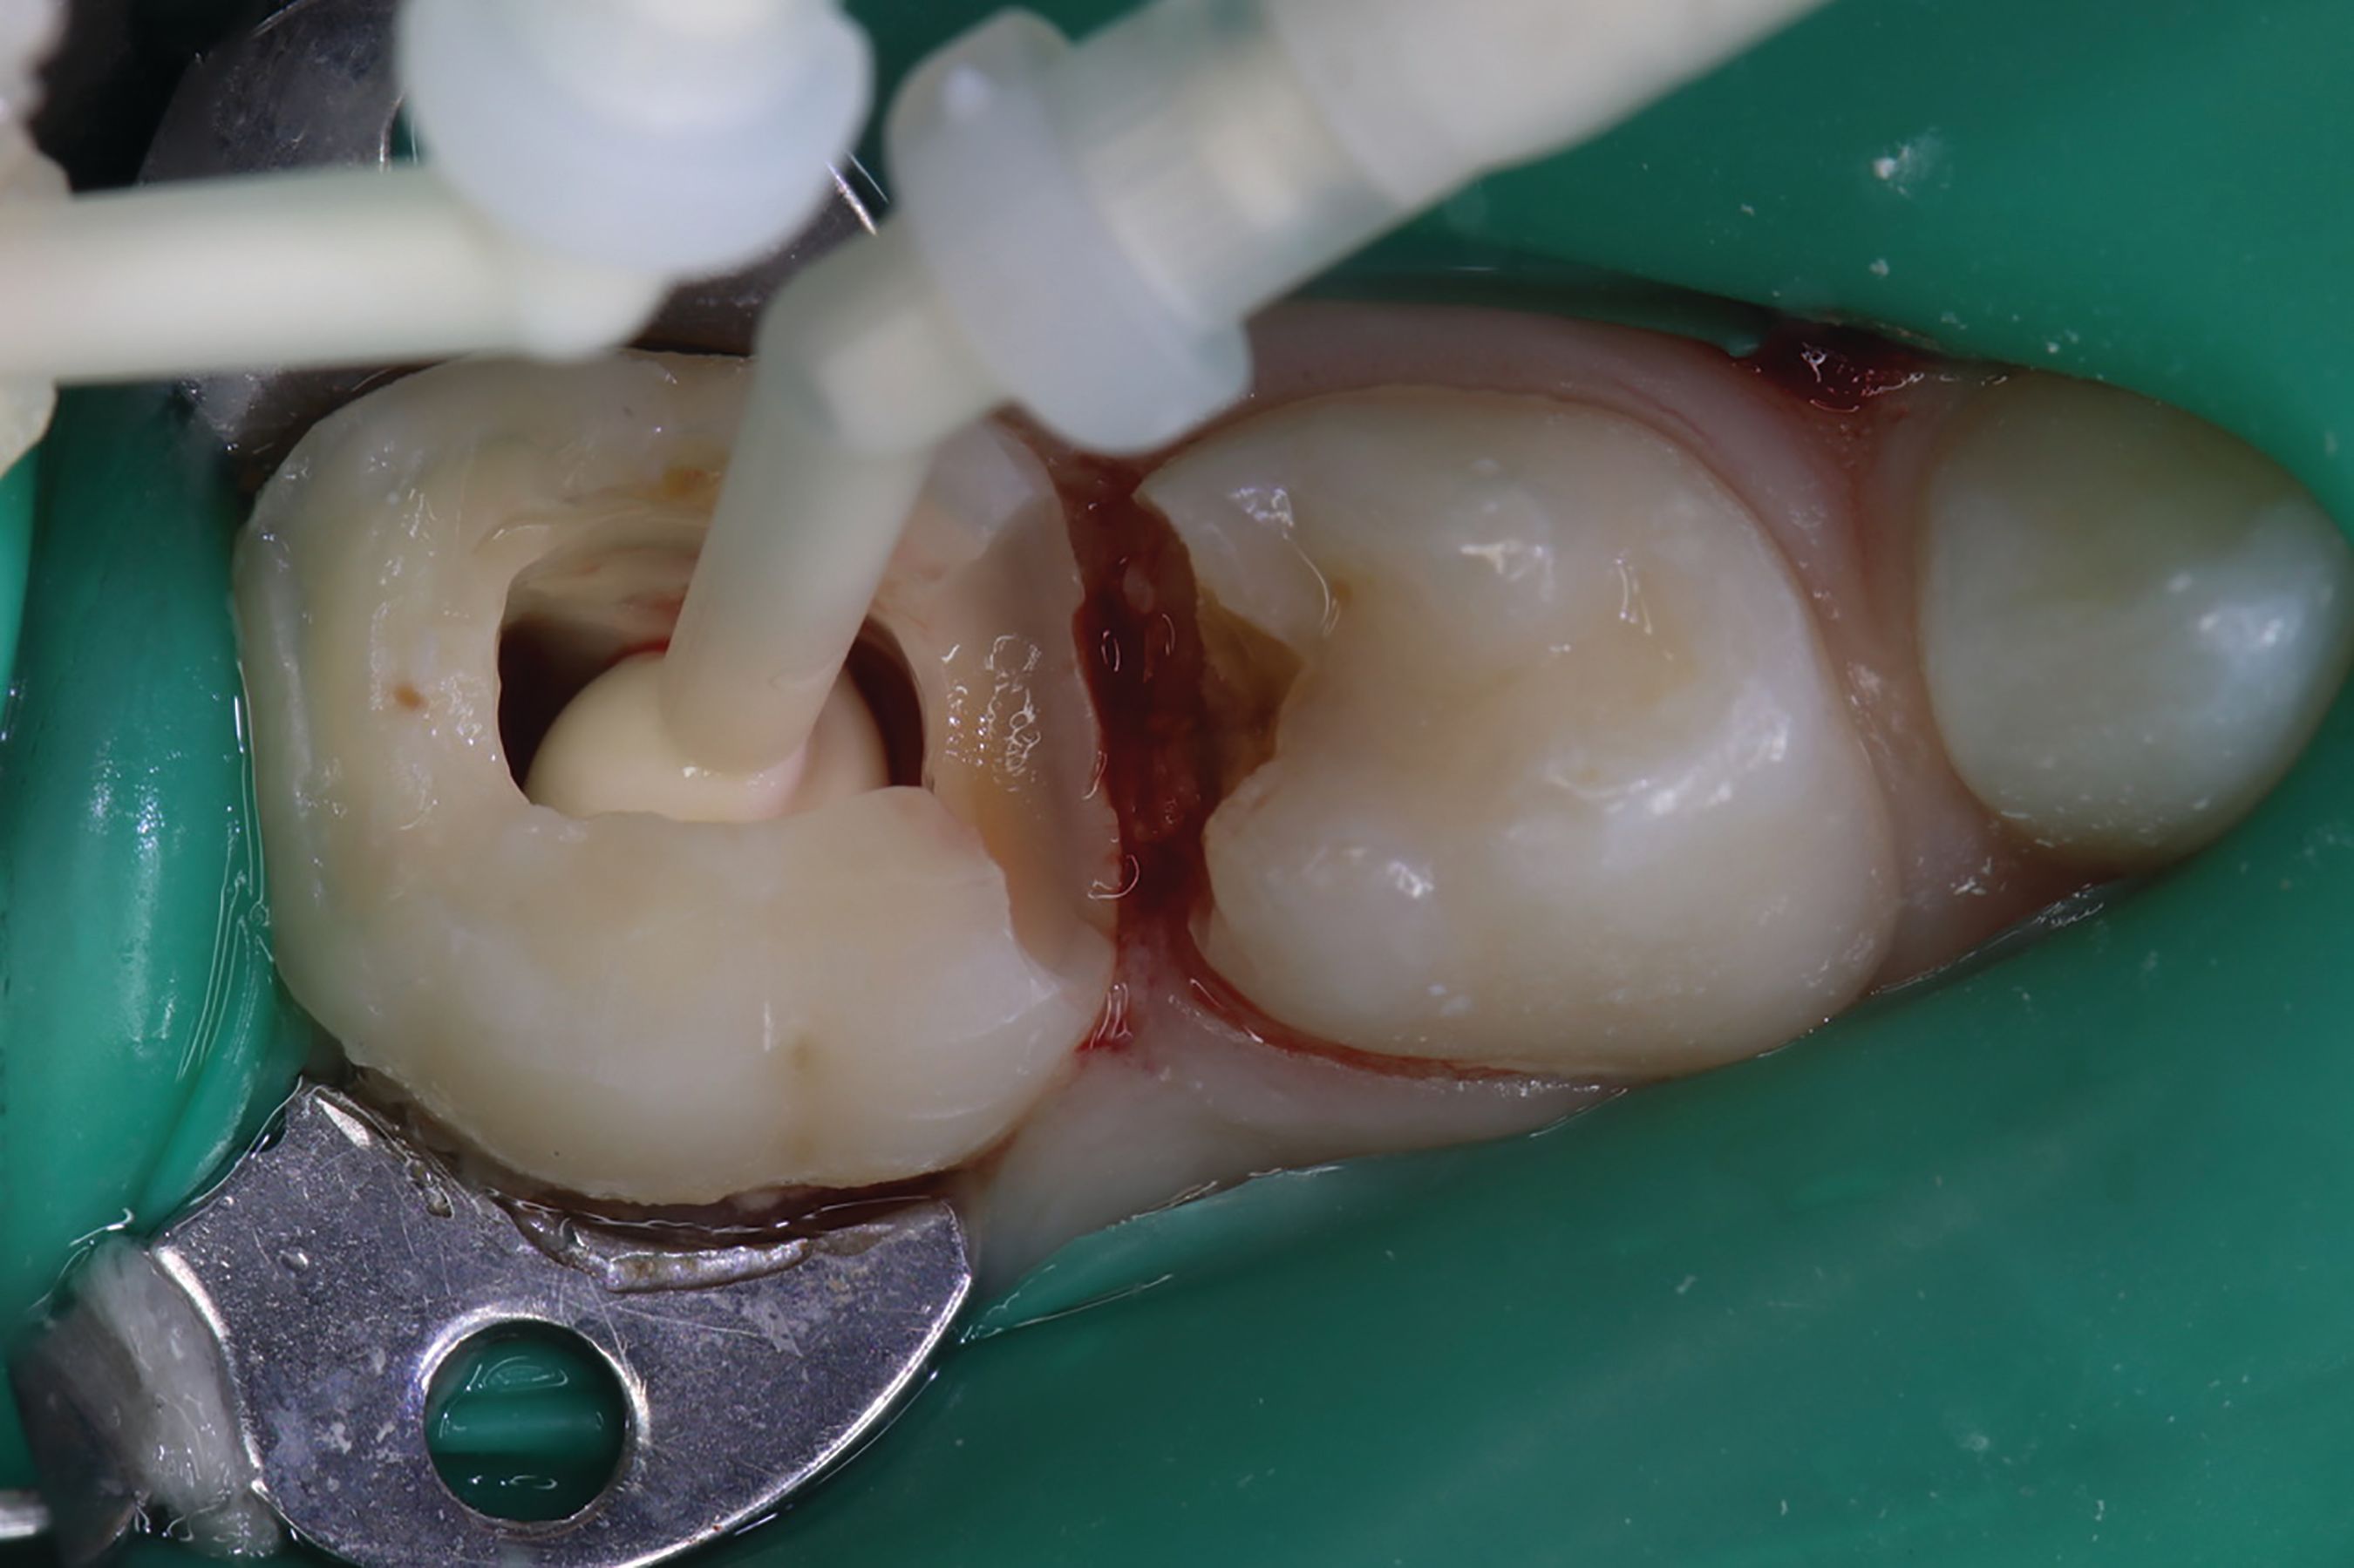

Amputation of coronal pulp chamber to the level of radicular pulp stumps was performed with NSK Dental slow speed large round bur #8, removing coronal pulp tissue with gentle upward motion (Fig. 2). Hemostasis is achieved with a saline-soaked sterile cotton pellet (Figs. 3-4). Figure 5 also illustrates hemostasis.

Fig. 3

[ Figs. 1-9 ] Pre-operative view-primary second molar requiring pulpotomy procedure (Fig. 1). Amputation of coronal pulp chamber to level of radicular pulp stumps with NSK Dental’s slow speed large round bur #8, removing coronal pulp tissue with gentle upward motion (Fig. 2). Hemostasis achieved with saline-soaked sterile cotton pellet (Figs. 3 & 4). Hemostasis achieved (Fig. 5). Extrusion of TheraCal PT into pulp chamber, being sure to reach base of coronal pulp chamber with material and without voids or bubbles and light cure (Figs. 6 & 7). Cured TheraCal PT (Fig. 8). Full-coverage stainless-steel crown (Fig. 9).